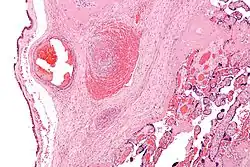

refer to caption

Micrograph showing a fetal (placental) vein thrombosis, in a case of fetal thrombotic vasculopathy. This is associated with cerebral palsy and is suggestive of a hypercoagulable state as the underlying cause.